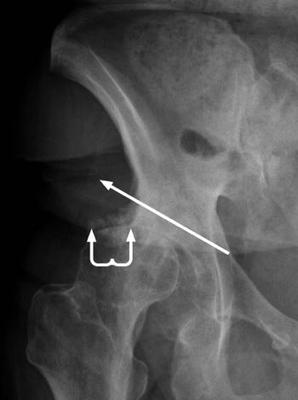

Two weeks ago I fell landing on my right top femur. Sore but no problem. Then 3 days ago after some lifting of fairly light boxes, it began again but this time it is severe in the sacral area as well as pelvic bone area, groin, right hip including upper right front thigh. Also noted bone pain. ER visit again, x-ray negative, pain meds and muscle relaxers prescribed, heat recommended.

I would dearly like to see a copy of that x-ray. Could you get help in sending them to contact?